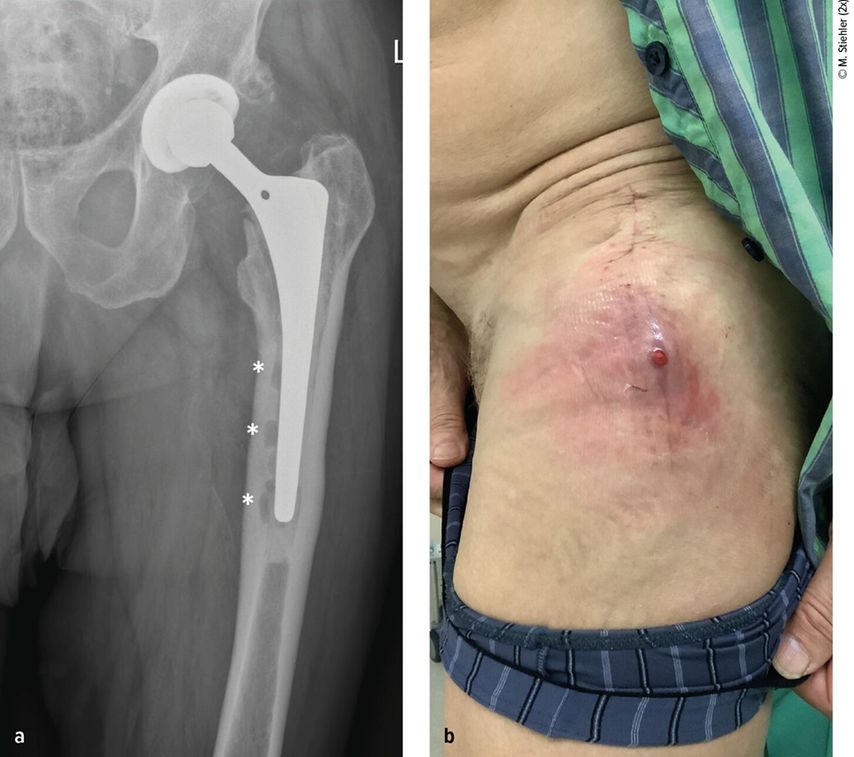

Anhand der klinischen Zeichen und der Symptomdauer unterscheidet man zwischen akuter und chronischer PPI. Die akute PPI ist durch eine kurze Symptomdauer (<3 Wochen) charakterisiert. Sie tritt entweder in der frühen (<4 Wochen) Phase nach endoprothetischem Gelenkersatz (akute postoperative PPI) oder aber verzögert (>4 Wochen, ggf. erst mehrere Jahre) nach Endoprothesenimplantation im Rahmen einer hämatogenen Streuung eines endoprothesenfernen Infektionsherdes (akute hämatogene PPI) auf. Typischerweise imponieren hier lokale Infektionszeichen wie Schmerzen, Schwellung, Rötung, Überwärmung oder eine prolongierte Wundsekretion (>7 Tage). Die Unterscheidung zwischen akuter und chronischer PPI basiert auf den Eigenschaften des bakteriellen Biofilms. Beim Vorliegen einer akuten PPI ist von einem unreifen bakteriellen Biofilm auf der Endoprothesenoberfläche auszugehen. Bei der chronischen PPI (>4 Wochen postoperativ) mit längerer Symptomdauer (>3 Wochen) liegt hingegen ein potenziell reifer Biofilm vor. Die klinischen Symptome sind in der Regel weniger ausgeprägt. Jedoch kann das Vorliegen einer kutanen Fistel oder von radiologischen Zeichen der Endoprothesenlockerung auf eine chronische Infektion hinweisen (z. B. Abb. 1).